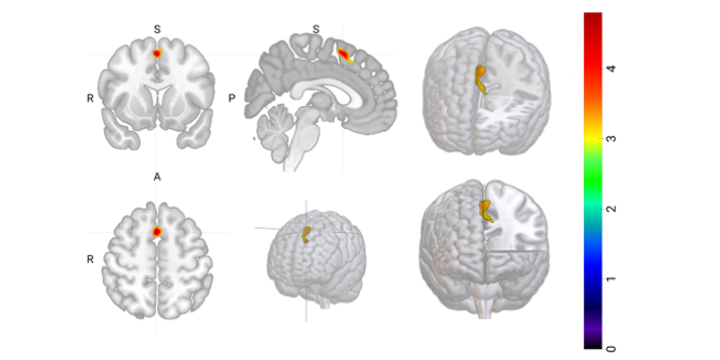

Across two independent samples of young adults, we consistently linked greater activity in the pre-supplementary motor area (pre-SMA) to higher BAS Fun Seeking, an impulsivity facet capturing the drive for excitement and novelty. The pre-SMA functionally sits at the crossroads of motivation and action initiation, helping translate internal urges into planned — or impulsive — behavior, which made it a prime candidate for capturing approach-related vulnerability in bipolar disorder. Replication was a top priority from the start. Despite differences in participant profiles, scanners, and symptom levels between cohorts, the core pattern remained robust, reinforcing our confidence that this reflects a meaningful signal rather than noise.

The real revelation, however, was how current mood modulated this link. As current depressive symptom severity increased, the association between pre-SMA hyperactivity and Fun Seeking weakened significantly. Importantly, this was not due to reduced pre-SMA activity itself — the neural signal stayed robust. Instead, its translation into Fun Seeking was dampened, masked by affective state. Together, our results point to impulsivity as a latent neural drive that persists across mood states in bipolar vulnerability, but whose behavioral expression is gated by current affective state.

Clinically, this is critical for bipolar disorder. Relying on behavioral observation or self-report alone risks underestimating vulnerability during depression, when impulsivity hides rather than disappears. A stable neural marker like pre-SMA hyperactivity during reward anticipation could provide a more trait-like index of mania/hypomania risk, potentially aiding earlier detection, monitoring across episodes, or guiding intervention. Targeted neuromodulation of the pre-SMA has already shown promise in reducing impulsivity in related disorders, and these findings suggest it may be a relevant target in bipolar vulnerability as well.